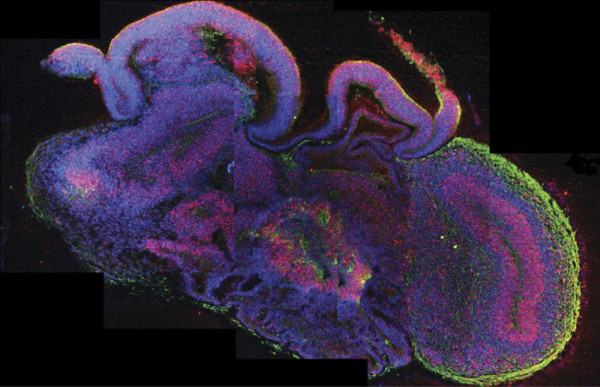

Un equipo de científicos europeos ha desarrollado pequeños cerebros humanos tridimensionales, de cuatro milímetros de diámetro, a partir de células madre pluripotentes que ayudarán a profundizar en el estudio de las enfermedades neurológicas, informó hoy la revista científica 'Nature'.

Estos órganos artificiales, fruto de una investigación conjunta de la Universidad de Bonn (Alemania) y el Instituto de Biotecnología Molecular de Viena (Austria), aportan importantes avances sobre el desarrollo del cerebro durante las etapas más tempranas y sus patologías.

Estos microcerebros, que incluyen la corteza cerebral que cubre los dos hemisferios, están formados por diferentes tejidos dispuestos en capas, cuya organización guarda muchas semejanzas con la de un cerebro en sus etapas más tempranas de desarrollo.